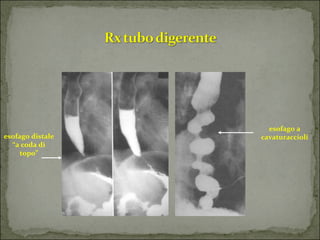

esofago

a

distale

cavaturaccioli

“a

coda

di

topo”

Immagini radiologiche